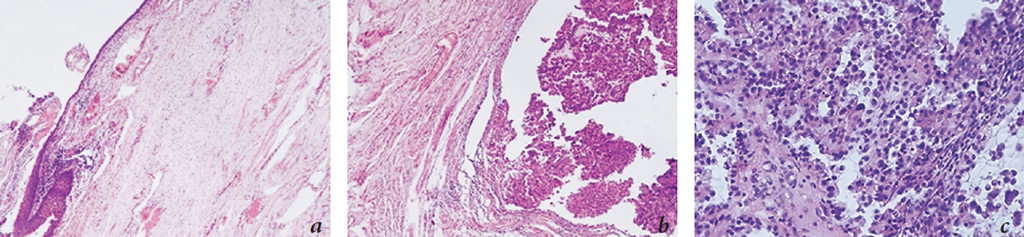

Surgery course. A densely elastic tumor around the urethra was revealed intraoperatively (Fig. 2), which was easily isolated from the surrounding tissues. It was decided to excise the tumor with a fragment of the urethra, while preserving the urinary bladder neck and distal segment of the urethra with the imposition of a cystourethroanastomosis. The excised tumor was a round-shaped, tight-elastic formation located around the urethral fragment (Fig. 3). On the macro-preparation, there was no visually exophytic growth in the urethral lumen, and the mucous membrane was pellucid and focal hyperemic. When the surgical material was excised, a fragment of an elastic whitish tumor tissue of 4 × 3 × 2 cm in size with an adjacent lamellar segment of the urethra of 3 × 2.5 cm in size and 0.2 cm thick was described. The histological examination revealed papillary growths of an immature tumor of the tubular-papillary structure of cells with clear protoplasm and the presence of cellular-nuclear polymorphism, which has a clear cell carcinoma structure along the outer surface of the urethra with an ingrowth into the muscle layer of the urethra. The mucous membrane of the urethra has a plethora, without tumor growth (Fig. 4). Thus, the anatomicopathological stage according to the T gradation was pT2. The patient was discharged from the hospital on day 12 after the surgery. At the time of discharge, she had no urine continence and was using diapers.

Fig. 4. Histological preparations of the urethra with a tumor: a – the mucous membrane of the urethra, there is no tumor growth (stain hematoxylin-eosin, ×40); b – clear cell carcinoma with invasive growth in the outer layers of the urethra (stain hematoxylin-eosin, ×100); c – clear cell carcinoma of the urethra (stain hematoxylin-eosin, ×200)

Рис. 4. Гистологические препараты уретры с опухолью: a — слизистая оболочка уретры, роста опухоли нет (окраска гематоксилином и эозином, увеличение ×40); b — светлоклеточная карцинома с инвазивным ростом в наружных слоях уретры (окраска гематоксилином и эозином, увеличение ×100); с — светлоклеточная карцинома уретры (окраска гематоксилином и эозином, увеличение ×200)